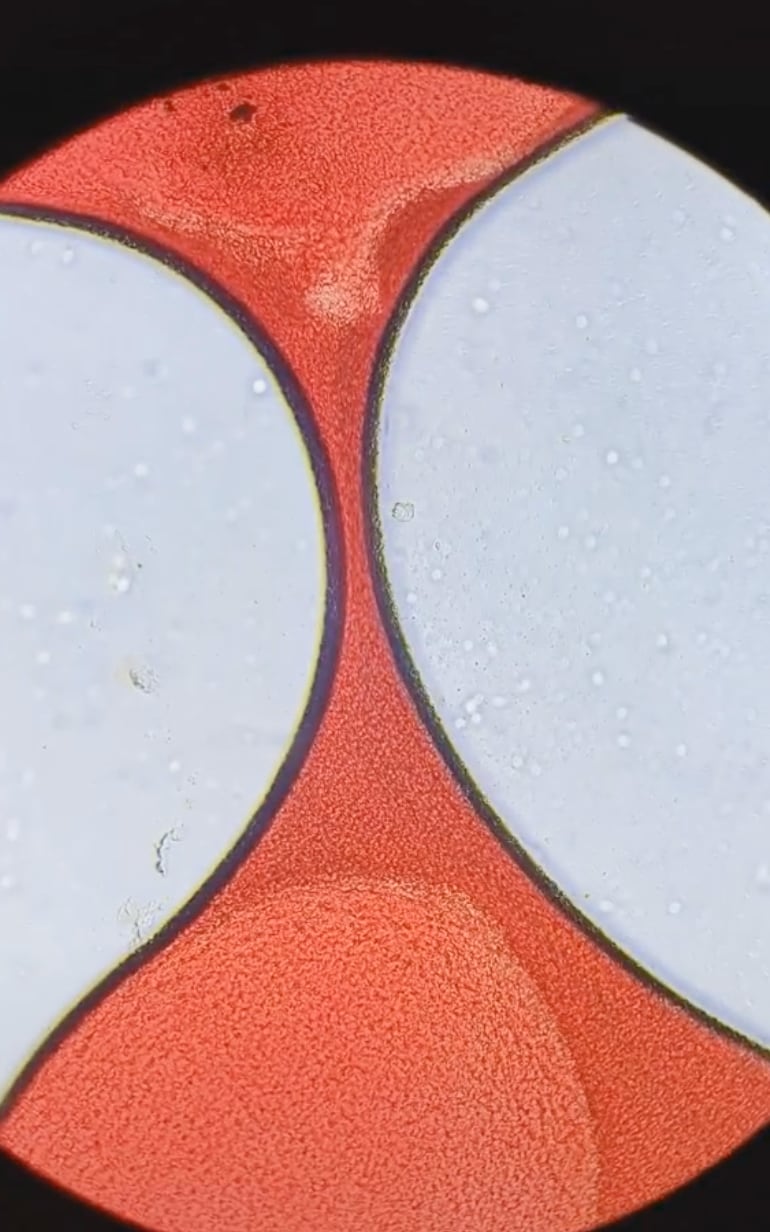

El coágulo de sangre menstrual es una mezcla de células sanguíneas, tejidos del revestimiento del útero y proteínas.

Primero, el experto colocó el coágulo de sangre menstrual en las placas del microscopio.

“Tienen una textura espesa similar a la gelatina”, describió.

El coágulo de sangre menstrual es de color rojo intenso; tal como describe el audio, tiene una consistencia muy espesa.

Con más aumento del microscopio, fue posible ver las células de sangre que “corren” por el coágulo menstrual.

Resulta fascinante observar el camino de las células que componen el coágulo de sangre menstrual.